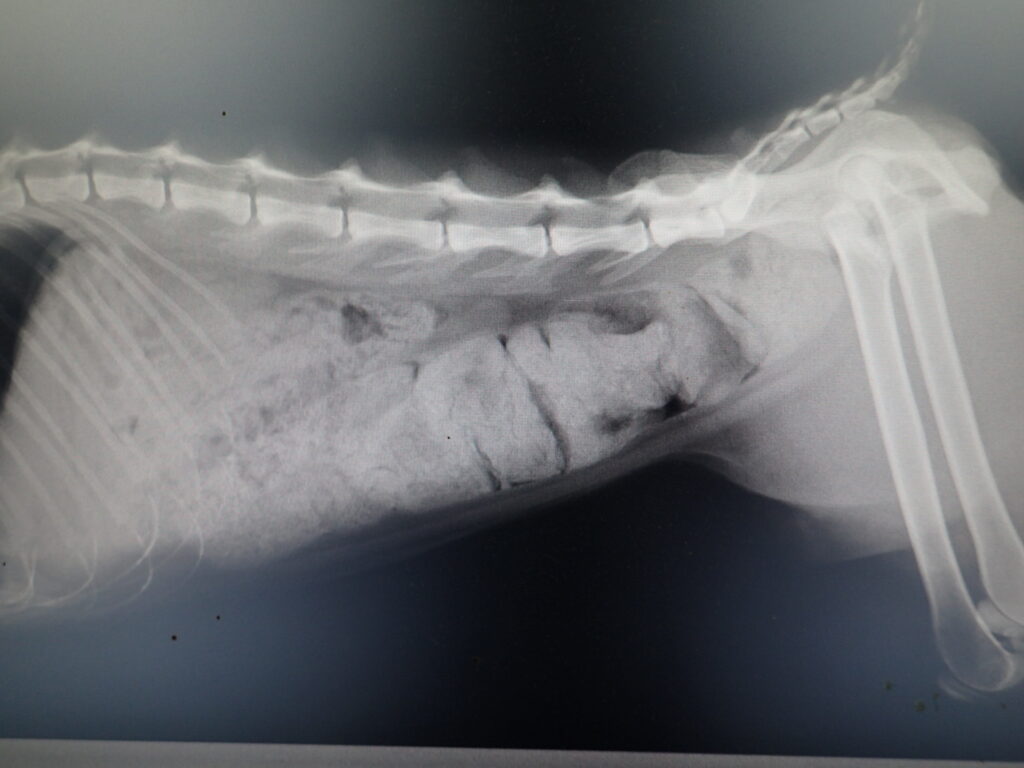

投与量を増やすにつれ、排便が軟らかくなった

シアルマリン(粉末)2g/day7日間投与 その後 (粉末)4g/dayを7日間投与 (粉末)5g/dayを7日間投与